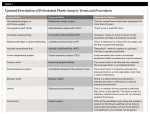

Currently, dentistry also has a more complete understanding of the role of interdental papilla. This article presents a new classification of papilla form that points out the significance of the width and height of the papilla. Also, because there is some confusing periodontal terminology that warrants a revisit, a new classification of these terms-intended to be an updated, more accurate description of the terminology-will be presented (Table 1). The author will use these terms throughout the article.